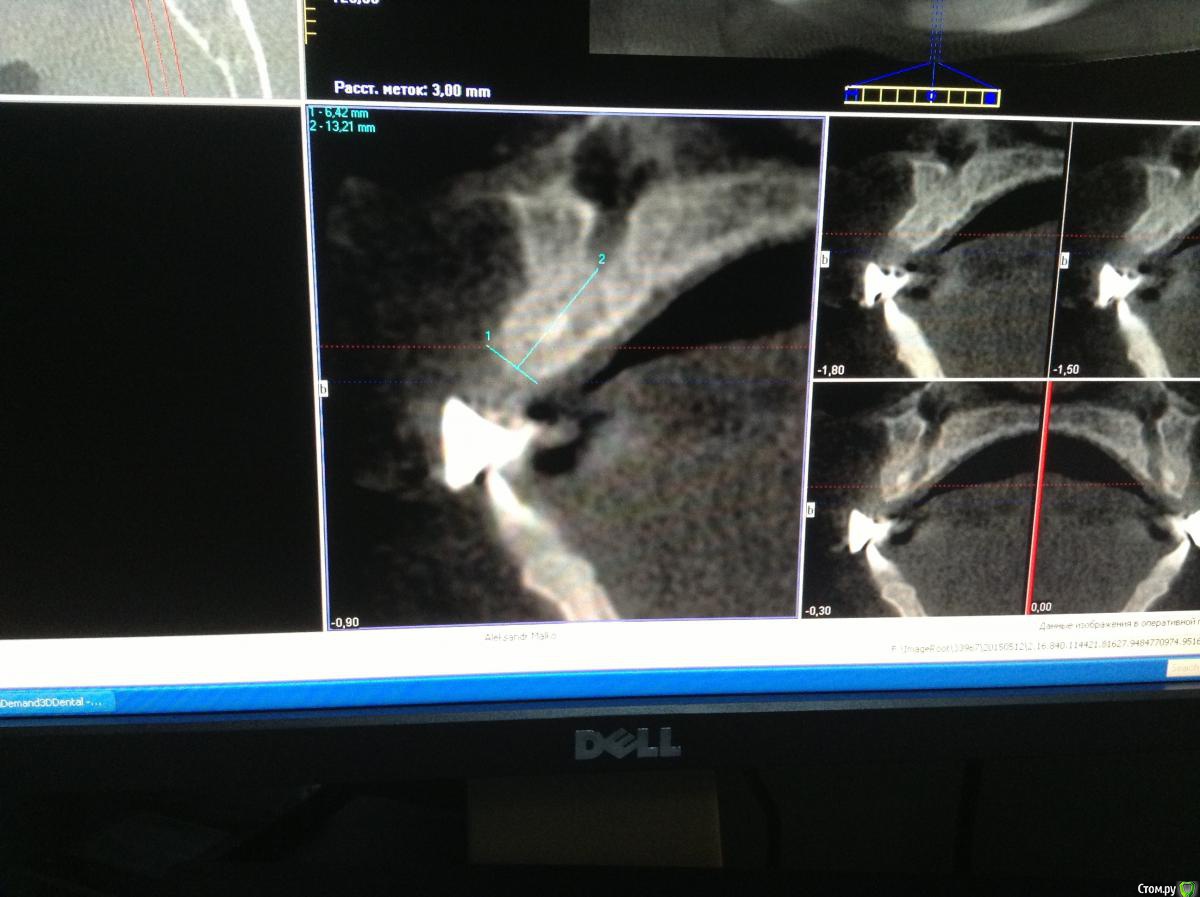

Romanson Опубликовано 5 июня, 2015 Поделиться Опубликовано 5 июня, 2015 Терапевты углядели резорбцию сказали сохранять не вариантА мост сняли уже? Как там с твердыми тканями 1.2? Если норм, то почему бы не попытаться спасти его? Всё-равно лоскут откидывать будете во время имплантации 1.1, так можно заодно ретроградно пролечить 1.2... А можно и не ретроградно, а просто под кальцием. Если положительной динамики не будет, то уж тогда удалять, а до этого времени он прослужит опорой для временной конструкции, если 1.1 одномоментно нагрузить не получится. А где терапевты резорбцию углядели, стрелочкой показать можете? Ссылка на комментарий

Гарриевич Опубликовано 6 июня, 2015 Поделиться Опубликовано 6 июня, 2015 Разделив на две операции я вижу только минусы.Однозначно оба импланта сразу в день удаления 12.если не трудно, покажите на снимке причины удаления 12хоть убей, не могу углядеть Ссылка на комментарий